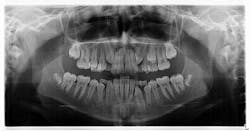

My hygienist had taken radiographs prior to me coming in.

Diagnosis: Mesiodens tooth

- Diagnosis is primarily via radiograph and can be confirmed by taking multiple angles using intraoral and extraoral radiographs (i.e., panoramic, periapicals, etc.). Furthermore, three-dimensional CBCT scans allow dialing in on the palatal location of the mesiodentes and their relationship to adjacent teeth. Delayed or altered eruptions of adult dentition also give rise to the suspicion of mesiodentes. Other common signs include cyst formation and crowding.